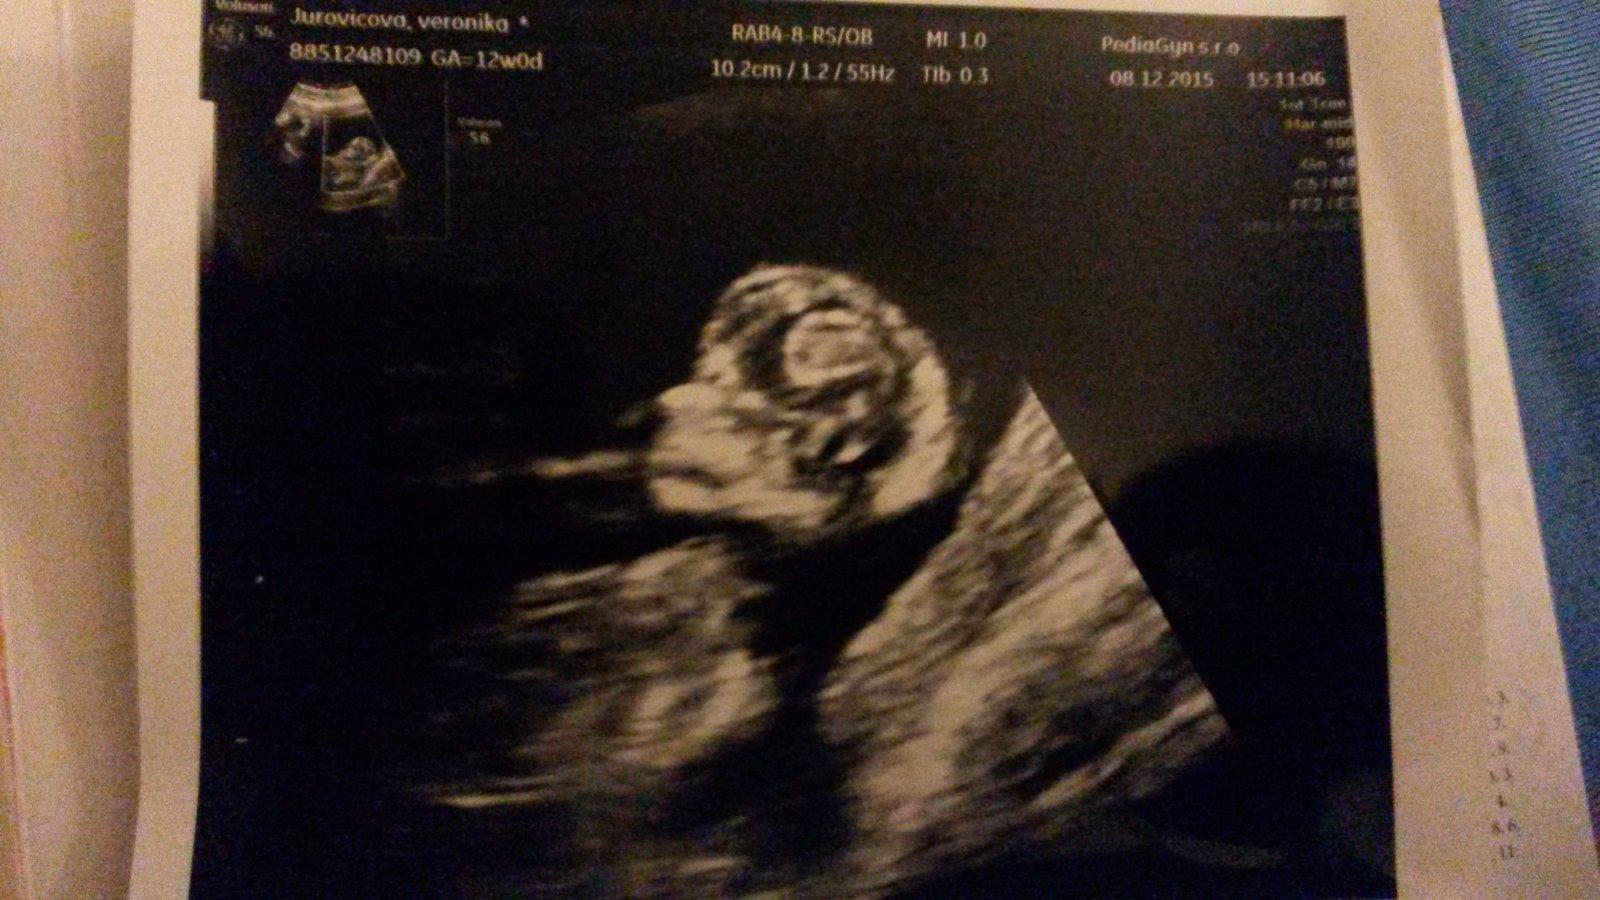

Ahojte damy tak tu je nas maly zazrak ocividne nie je narcis po mamine...absolutne nedpolupracovalo...stalo a nechcelo si lahmut. Takze len jedna foto. Podla son sme 12+5 podla ms 12+3. Na tie tripple testy idem 8 januara. A mimi ma 5 cm. Doktor slubil ze potom 8 mi vynimocne sptavi fotku aby som mala srdce na mieste inak sono az v 22 tt. Tak dufam ze aj dodrzi slovo mimi bude poozovat.

Ahojte, tak pridavam aj ja foto 12 tt a bábätko ma nieco vyse 5 cm 😃. Je to pohodak, cely cas si takto vegetilo ani sa nepohlo 😃. Vsetko je v poriadku. Tesim sa, lebo pri dcerke bol stale nejaky problem. Citim sa oveľa lepsie, minimálne nevolnosti a unava. Prajem vam krasne Vianoce, my to oznamime rodine pri stromceku 😃😊🎉. Tak sa tesim 😊 uzite si sviatky, mile tehulky .... 😄